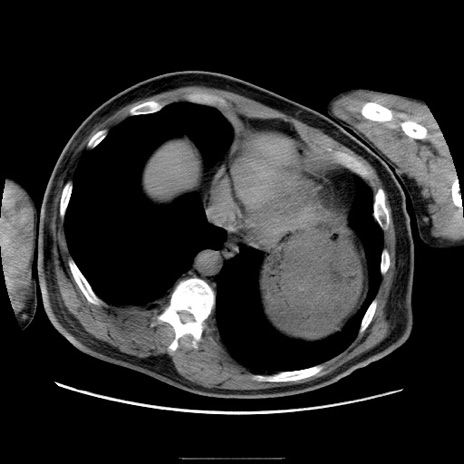

症例

冠状断像

【症例】50歳代男性

【主訴】腹痛

【現病歴】AVMからの被殻出血のため回復期リハ病棟入院中。 本日午後3時頃急に下腹部痛が出現した。

【既往歴】AVM、被殻出血、虫垂炎、高血圧

【身体所見】意識晴明、左半身不全麻痺、会話の理解は良好、36.5°C、腹部:膨隆、全体に板状硬、下腹部正中に圧痛点あり、反跳痛-、筋性防御不明、右下腹部にope scar

【データ】WBC 9400、CRP 0.06